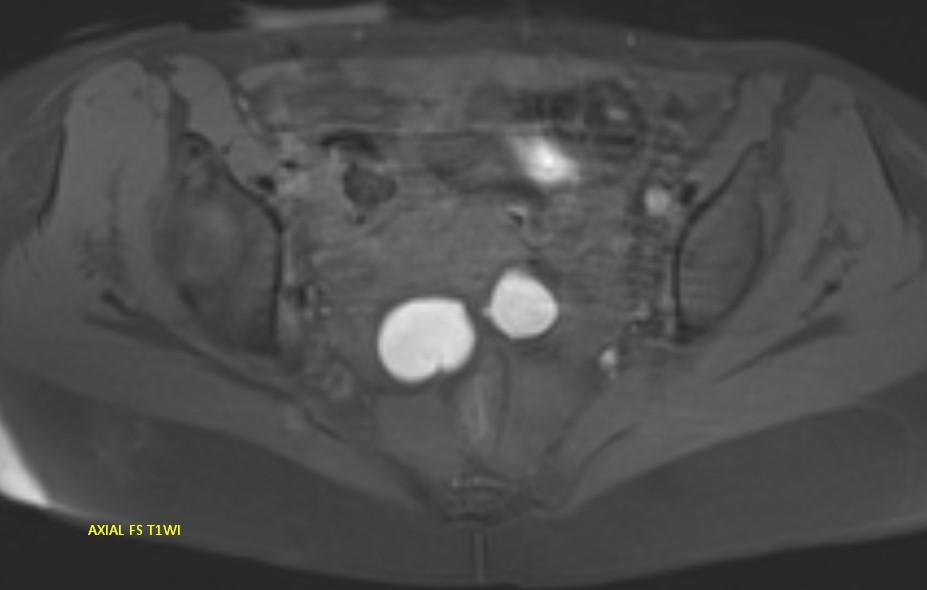

*23-year-old female with primary infertility.

Answer: Kissing Ovary Sign

MR images demonstrating the kissing ovaries, bilateral endometriomas (chocolate cysts), and peritoneal inclusion cyst (peritoneal pseudocyst).

Blood products in ovaries may cause adhesions to pull the ovaries toward the midline. This is considered a sign of pelvic endometriosis (1).